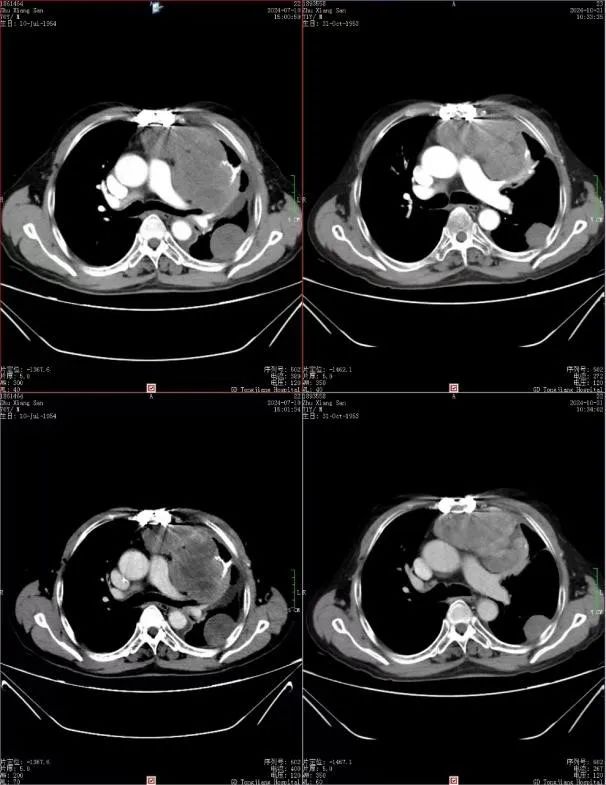

01 朱先生是一位与肺恶性肿瘤抗争多年的勇士。自确诊以来,他经历了多次复发和反复手术。2021年3月,胸部CT揭示了左下胸腔的占位性病变,随后的肺肿物切除术和化疗未能阻止病情的进展。2023年,局部复发再次降临,尽管再次手术和化疗,顽固的低血糖和双下肢浮肿等问题仍旧困扰着他。2024年6月,胸部CT显示肿瘤进展,胸膜心包膜受累,7月症状加重,他带着朋友的推荐来到我院寻求帮助。 AUTUMN 在朱先生的治疗旅程中,我们深刻理解他的痛苦与焦虑,并承担起责任。我们的专家团队为他量身定制了治疗方案:首先采用LATTICE技术精确打击肿瘤,结合替莫唑胺化疗、培唑帕尼抗血管治疗及激素压制的综合治疗方案。经过6次LATTICE治疗后,朱先生的病情得到了显著改善——肿瘤缩小,血糖稳定在正常水平,生活质量大幅提升。如今他已出院两月有余,享受着与家人共度的美好时光。这一成功案例是ky多学科会诊模式下,精准放疗中心和肿瘤科技术团队紧密合作的结果 探索革命性的LATTICE技术 LATTICE技术,即空间分割放射治疗技术,以其在肿瘤内部创造不均等剂量分布的原理,为肿瘤治疗领域带来新突破。这种先进的放射疗法特别适用于大肿块(任何尺寸≥5 cm)和放射抗性肿瘤,展现出其独特的优势:高剂量区精准定位于肿瘤内部,同时最大程度保护正常组织;显著改善症状;确切的肿瘤消退效果;以及卓越的局部控制率。